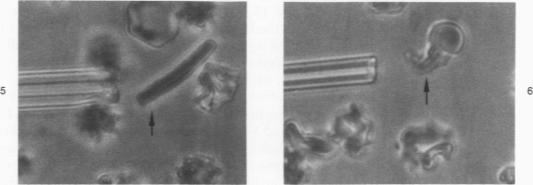

Modest increases in intracellular calcium concentrations, in association with ATP depletion, cause the appearance of pathologic changes in erthrocyte shape and deformability. The loss of erythrocyte ATP and simultaneous increase in cellular calcium have previously been considered the sole requisites for the appearance of erythrocyte membrane rigidity. We report that red cells suspended in high-potassium buffers may be simultaneously loaded with calcium (through exposure to the divalent cation ionophore A23187) and depleted of ATP without incurring drastic changes in shape or in membrane stiffness. Incubation of erythrocytes under these conditions effectively blocks both water and potassium loss normally caused by calcium accumulation. However, the high external potassium has no influence on either the ionophore-induced accumulation of calcium or on the the concomitant hydrolysis of cellular ATP. These results suggest the involvement of at least one further parameter, ie, changes in cell water and cation content, in the development of calcium-induced erythrocyte rigidity.

细胞内钙浓度的适度升高,与ATP耗竭相关联,会导致红细胞形状和可变形性出现病理变化。红细胞ATP的丧失以及细胞内钙的同时增加,此前一直被认为是红细胞膜刚性出现的唯一必要条件。我们报告称,悬浮在高钾缓冲液中的红细胞可能会同时加载钙(通过暴露于二价阳离子载体A23187)并耗尽ATP,而不会在形状或膜硬度上发生剧烈变化。在这些条件下孵育红细胞可有效阻止通常由钙积累引起的水和钾的流失。然而,高细胞外钾对载体诱导的钙积累或细胞ATP的伴随水解均无影响。这些结果表明,至少还有一个参数参与了钙诱导的红细胞刚性的发展,即细胞内水和阳离子含量的变化。